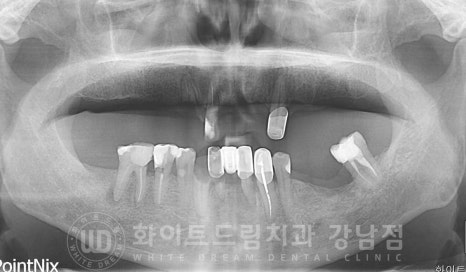

경기도 김포에서 내원을 해주신 70대 남성분이십니다.

치과 치료에 대한 공포감이 있으셔서 치료를 치일 피일 미루고만 계셨다가

저희 강남 화이트드림치과를 소개받아 내원해 주셨습니다.

초기 구내 사진을 보면 상악 치아들은 대부분 없으신 상태로

남아있는 보철과 치아의 상태가 좋지 못하신 분입니다.

보철들도 20년 가까이 돼가면서 겉면에 치아색상으로 씌어놓은 도자기가 모두 벗겨져

내부 메탈이 겉으로 드러나있어 심미적으로도 굉장히 좋지 못한 상태였는데요.

환자분은 남아있는 치아들 중 23, 34, 44번 치아를 조금 더 사용하실 수 있으신 상태였으나

'이번에 큰마음 먹고 진행하는 김에 다 임플란트로 교체하고 싶어요'

이야기를 하셔서 환자분의 결정에 따라 전체 발치 후 임플란트 치료를

진행하기로 결정되었습니다.

상악동의 경우 개인마다 모양, 위치, 크기가 각기 다른데

환자분의 경우 상악동의 위치가 높게 자리를 잡고 있는 상태입니다.

상악동이 높게 자리를 잡고 있으면

잇몸뼈의 길이가 임플란트를 식립하기에 적합하여 뼈이식 없이 수술이 가능한 경우들이 있습니다.

환자분의 경우 골 길이는 안정적이나

잇몸 염증으로 상악의 골폭 소실이 진행된 상태였습니다.